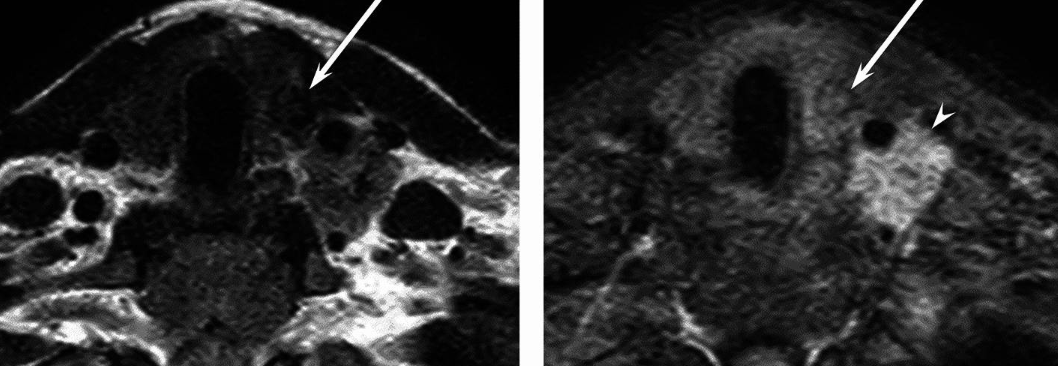

PTC is the most common thyroid cancer. On MRI, it usually appears as a solid mass with irregular margins, showing restricted diffusion (low ADC values) and is sometimes associated with lymph node metastasis. The solid components often display a hypointense signal on T2-weighted images compared to benign nodules. Ill-defined margins and extrathyroidal extension are also frequent.

Follicular carcinomas often appear brighter than normal thyroid tissue on T2-weighted scans and tend to stand out after contrast is given. The shape may be irregular, with edges that are not clearly defined. Sometimes you may see a thin dark rim around the tumour, but if this rim is incomplete or broken, it suggests the tumour has pushed through its capsule and may also show areas where it is invading blood vessels18,19. These changes help doctors distinguish follicular carcinoma from less harmful lumps, even when their signal is otherwise similar.